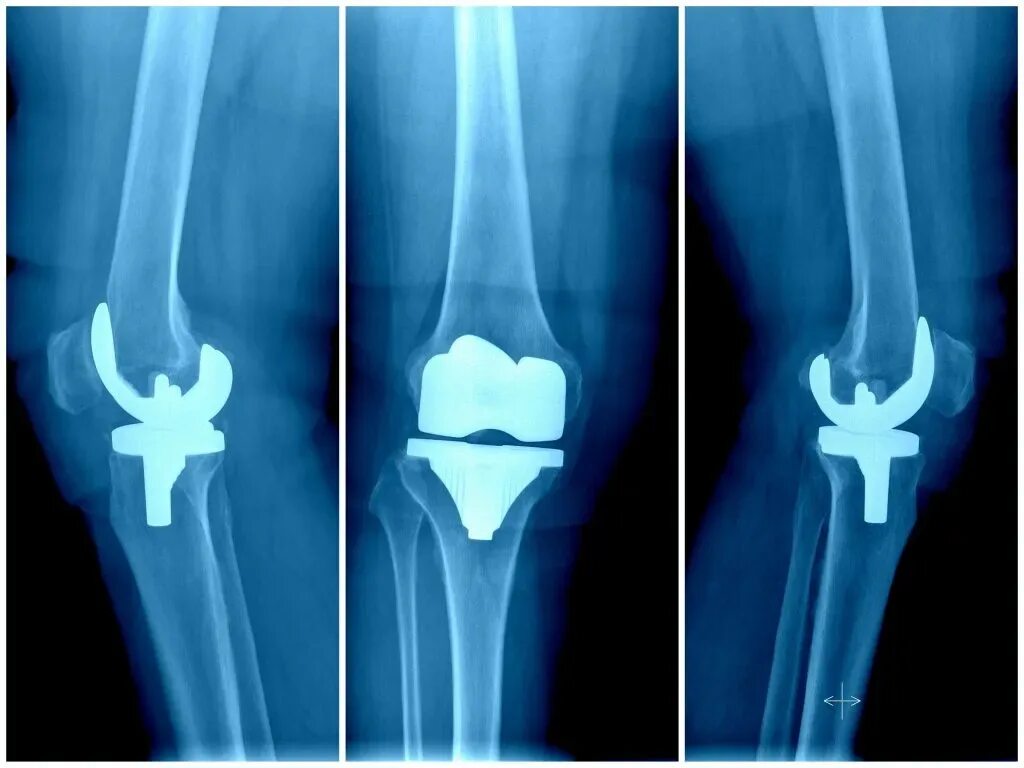

Эндопротезирование коленного после операции сколько болит